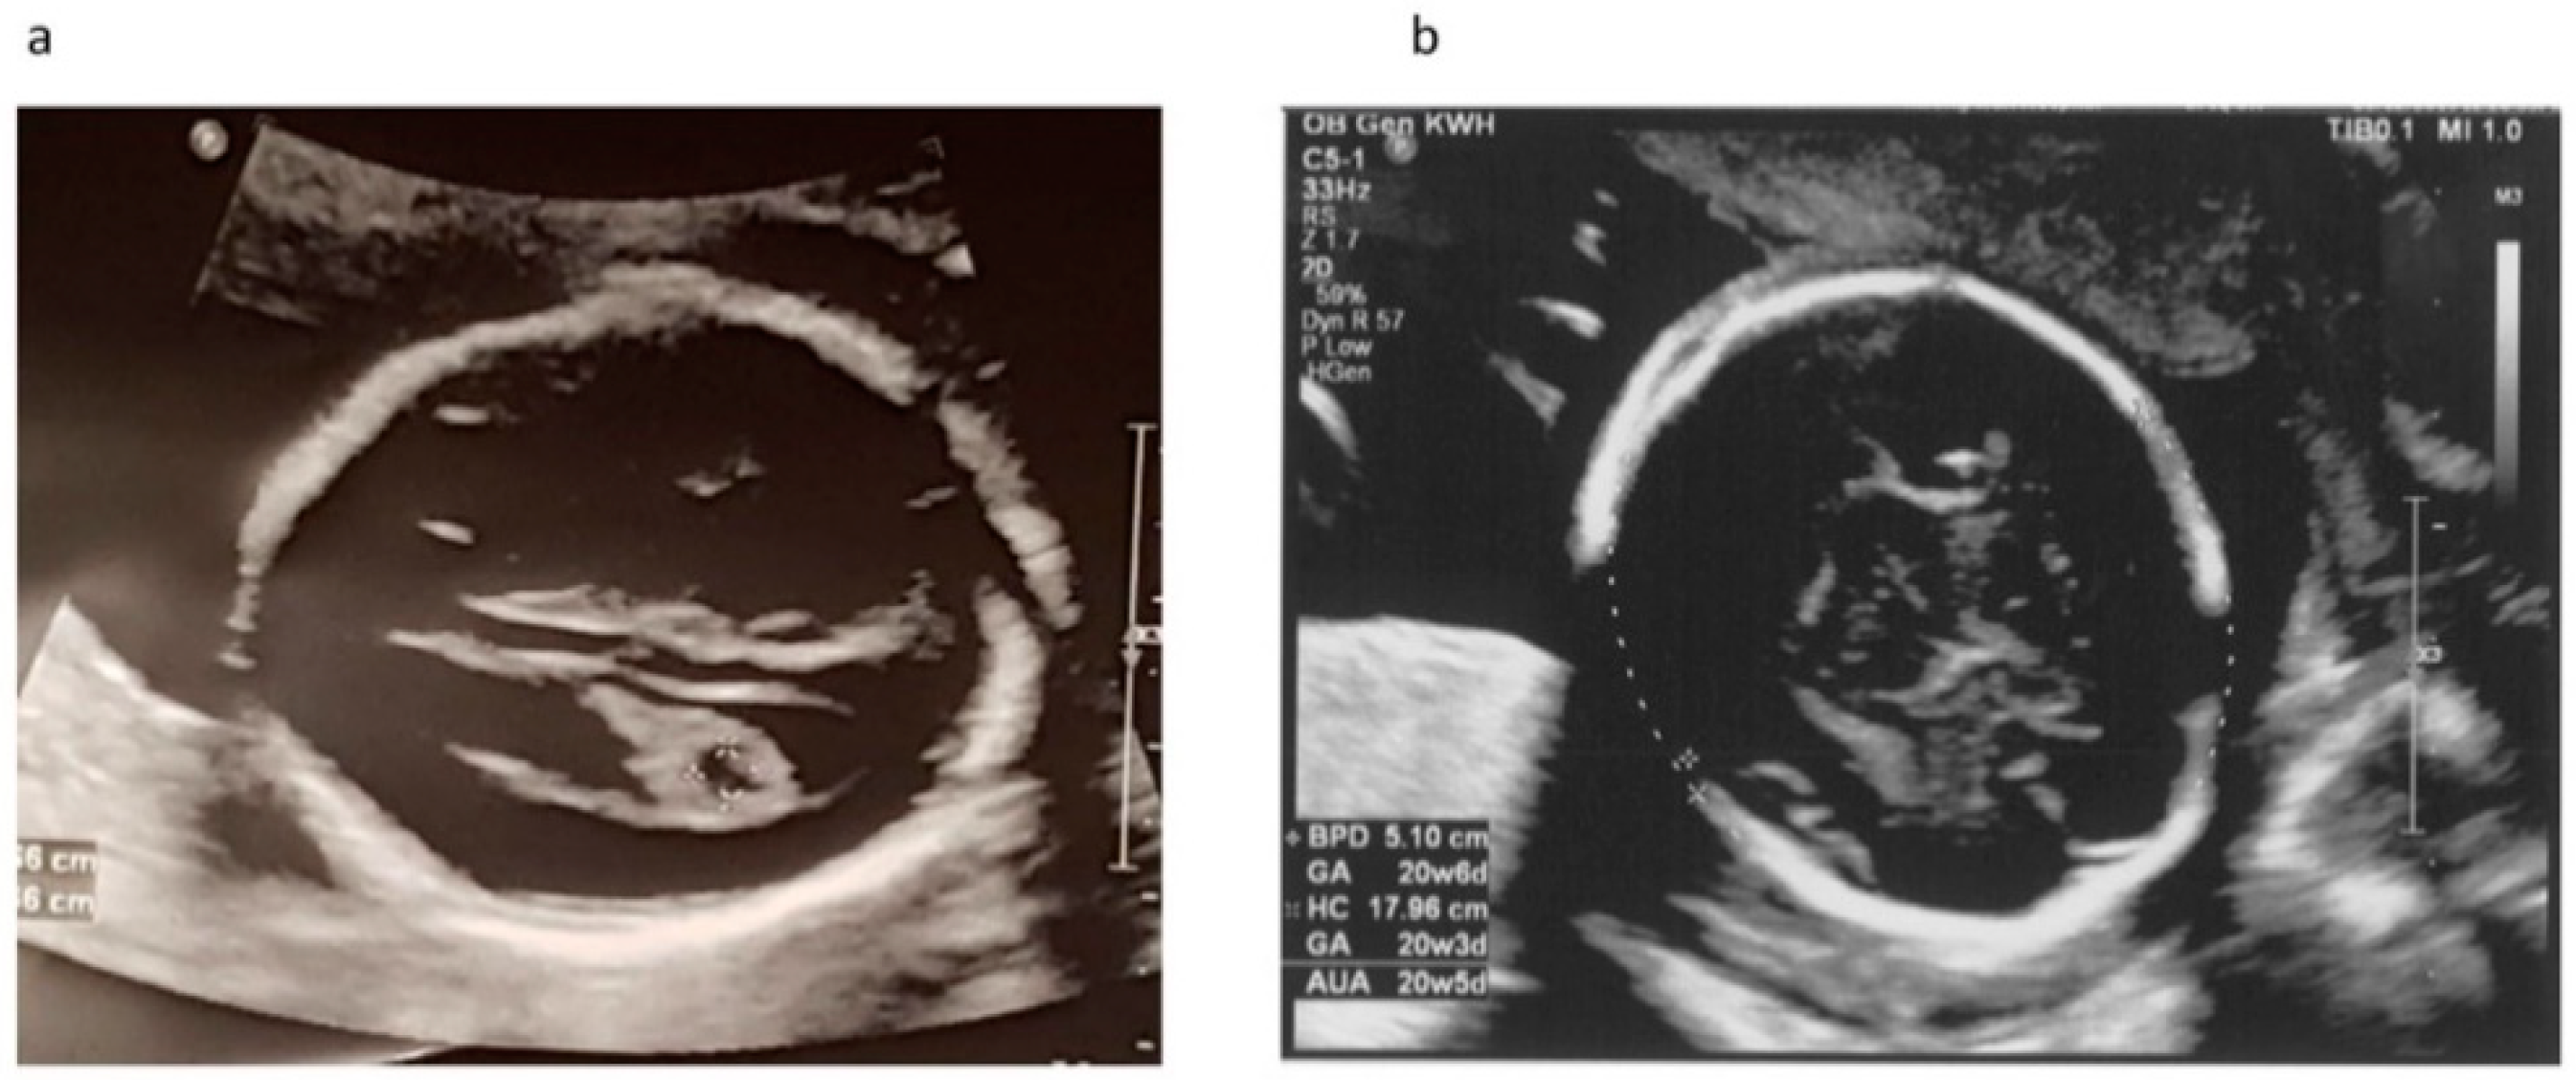

2. Case Report